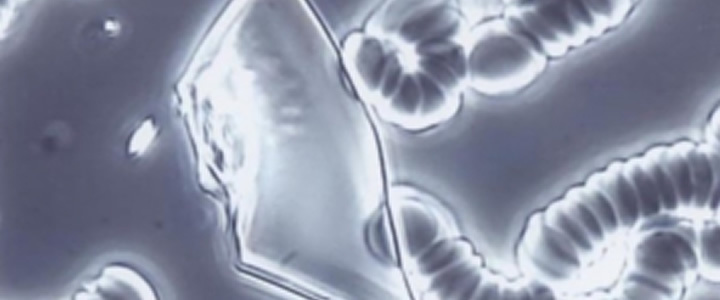

超音波診断(甲状腺・頚動脈・リンパ節などの表在・心臓・腹部・足の関節:痛風)